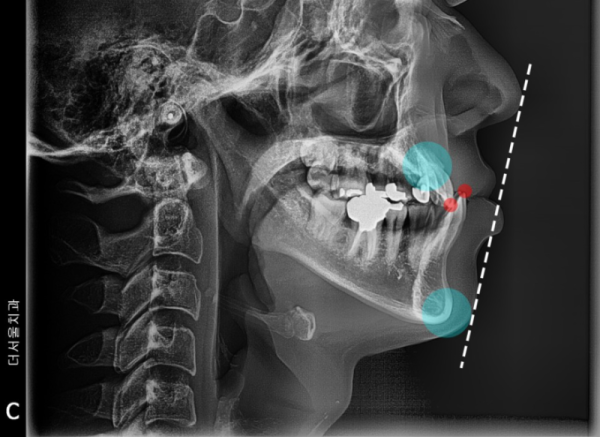

치아 부정교합 3급, 즉 주걱턱은 아래턱이 윗턱보다 전방으로 나와 있습니다.

이런 경우에는 양악수술을 통해 해결을 하는 경우가 많은데, 저희 성남치과 더서울치과에서

비수술로 인비절라인 투명교정 장치를 통해 주걱턱 개선을 한 증례입니다.

이러한 부정교합 3급의 경우에는 다양한 부작용이 있을 수 있습니다.

3. 턱관절의 악영향이 있을 수 있다.

주걱턱을 오래 두면 둘 수록 안면 비대칭이나 턱관절에 좋지 않은

악영향이 계속 일어날 수 있기 때문에 빠르게 교정치료를 받는게 좋습니다.